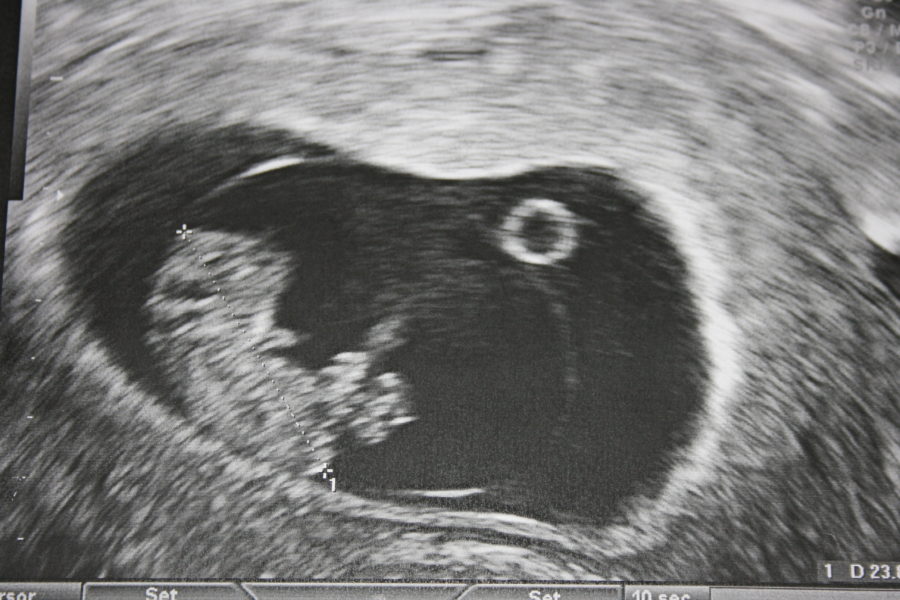

W hen a child is developing inside the mother’s womb, he is connected to his mother’s placenta through an umbilical cord which is attached to his abdomen/navel. It is a channel which carries the oxygenated blood and the all the required nutrients from the placenta to the fetus and as well carry the deoxygenated blood and waste products back from the fetus to the placenta. What does the cord string have? The average 50 cm long navel string comprises of the following. - A vein which carries the oxygenated blood and nutrients to the fetus - Two arteries which help in passing out the deoxygenated blood and waste products to the placenta - These two blood vessels are enclosed in a gelatinous substance called Wharton’s jelly which serves as a protection shield. Towards the end of the pregnancy period, the umbilical cord also serves the function of passing the antibodies to provide him with the immunity which he will need for about three months after being born. After the baby is born, the umbilical cord is clamped and cut. The portion of the placenta and the umbilical cord contain a little amount of blood which is called the cord blood. It contains all the basic elements of blood viz RBCs, WBCs, blood platelets and plasma. Additionally, it contains hematopoietic stems cells which can be used as transplantation alternative to the bone marrow. [Photo: sites.google.com]